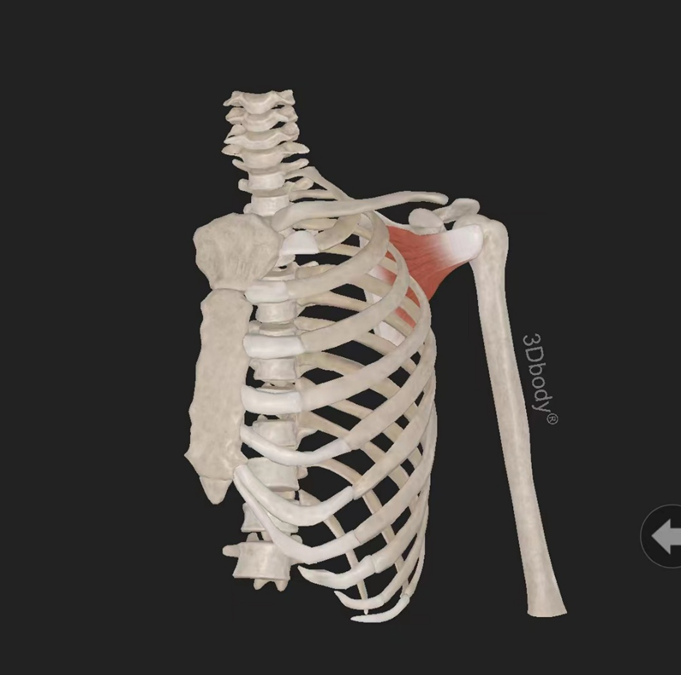

三角肌:起自锁骨外1/3、肩峰、肩胛冈,由三束组成,止于肱骨三角肌粗隆,由腋神经(C5—7)支配。作用:使肩关节外展、后伸和旋外、前屈和旋内。

1、前屈:肩关节前屈主要由三角肌前部纤维、胸大肌锁骨部、喙肱肌、肱二头肌完成,其中三角肌前部纤维最明显。

2、后伸:肩关节后伸的肌肉主要有三角肌后部纤维、背阔肌、胸大肌的胸肋部、大圆肌和肱三头肌长头,其中三角肌后部纤维作用最大。

3、内收:主要有胸大肌、大圆肌、背阔肌、喙肱肌、肱二头肌长头,此外三角肌前后部纤维也有内收作用。

4、外展:肩关节的外展由三角肌(主要是其中间束)及冈上肌完成。当肩处于内旋或外旋位置时,三角肌在最外侧的部分是外展的主要肌肉,当肩外旋时外展肌力要更强些。